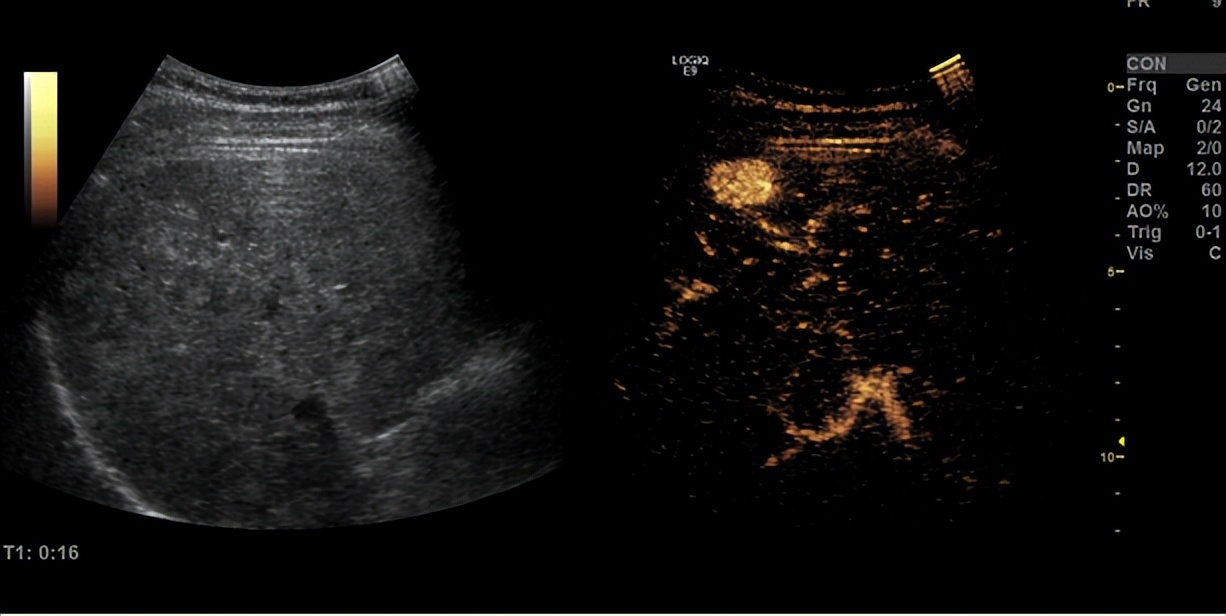

超声造影呈现“快进快出”模式,提示肝细胞肝癌